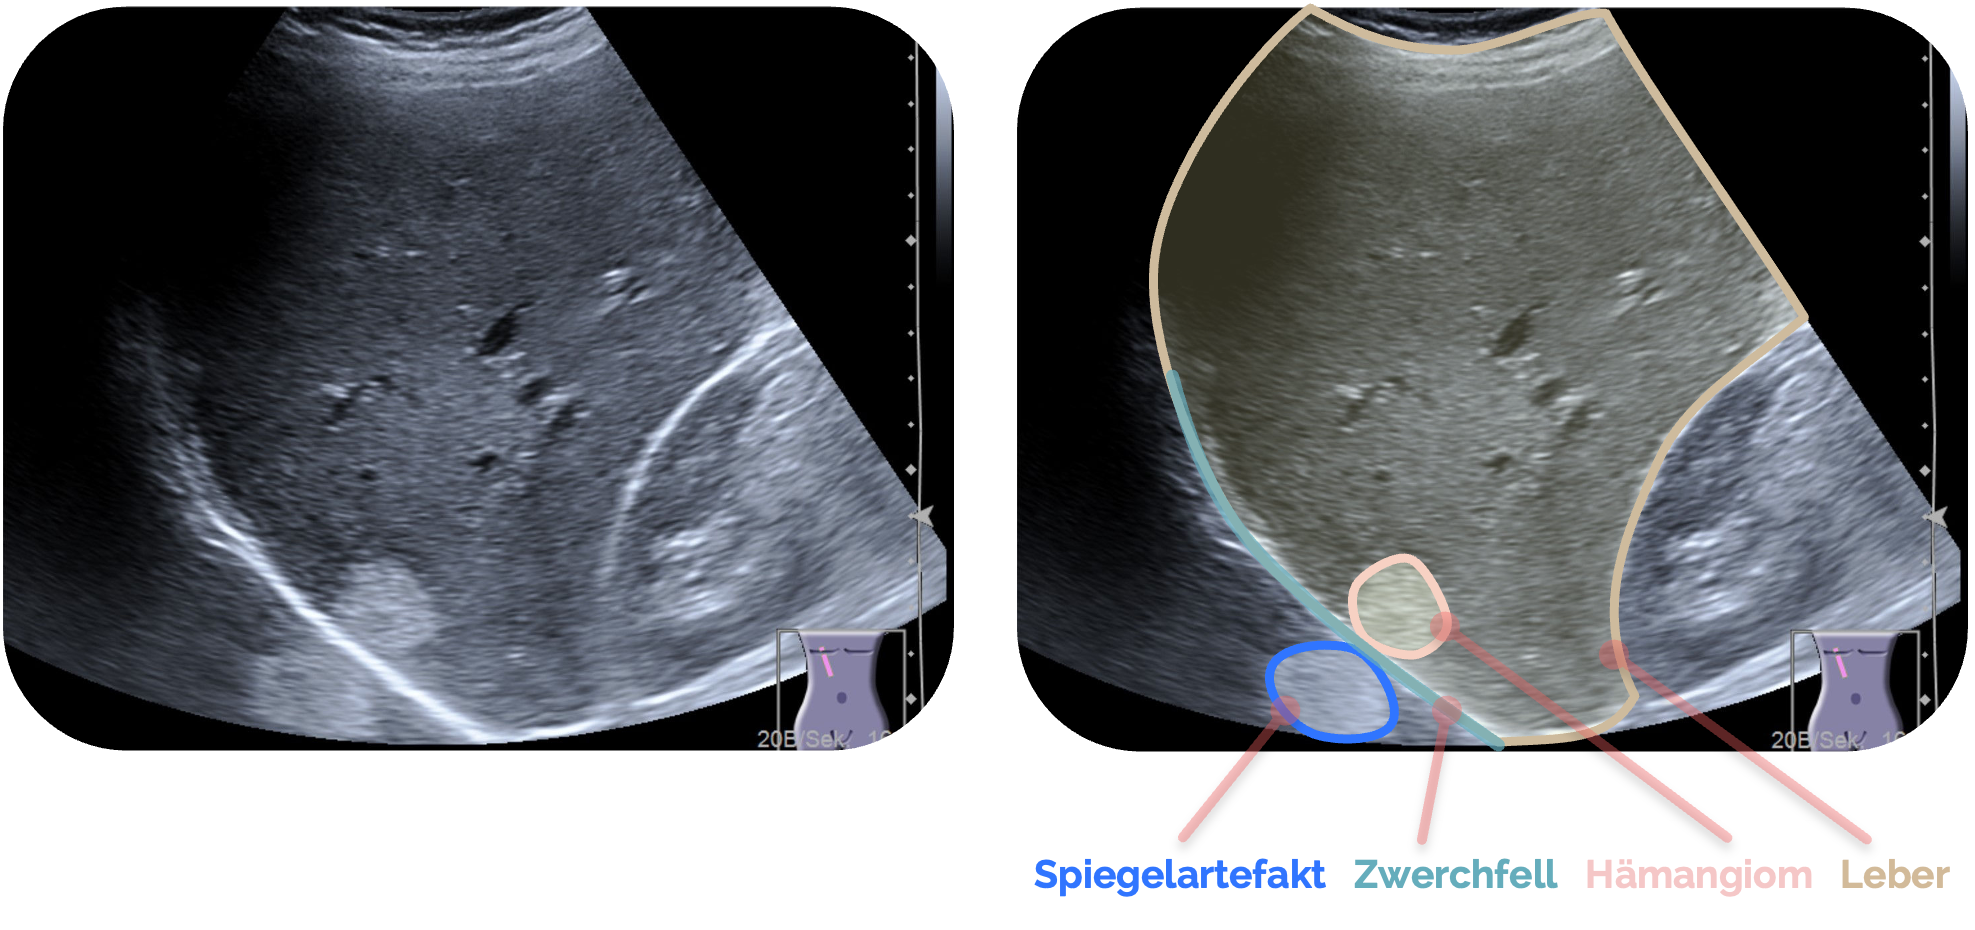

Spiegelungen:

Spiegelartefakte entstehen, wenn Schall auf eine stark reflektierende, glatte Grenzfläche trifft – meist Zwerchfell oder Pleura – und dabei zwischen Schallkopf, Struktur und Reflektor mehrfach reflektiert wird. Der Schall nimmt dadurch einen Umweg zurück zum Schallkopf.

Da das Gerät grundsätzlich annimmt, dass alle Echos geradlinig und direkt zwischen Sonde und Struktur verlaufen, wird das verzögert eintreffende Echo fälschlich in größerer Tiefe dargestellt. Der typische Effekt ist eine Scheinstruktur „unterhalb“ der reflektierenden Fläche, obwohl die reale Struktur nur einmal vorhanden ist.

Erkennungsmerkmale:

Merkmal

Beschreibung

Lage

Doppelte Struktur „unter“ einer hellen Reflexionslinie (z. B. Zwerchfell, Pleura).

Aussehen

„Spiegelbild“ ist blasser und unschärfer als das Original.

Bezug

Zwischen echter Struktur und Spiegelbild liegt meist eine stark reflektierende Linie.

Verhalten

Spiegelbild verschwindet oder verändert sich beim Schallwinkelwechsel.

Schallschatten der Rippen links und rechts der Bildmitte